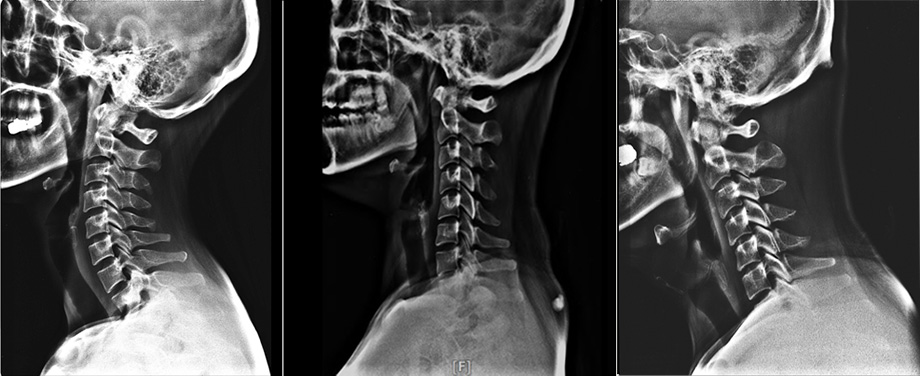

거북목이 있으면 목 뒤가 자주 뻐근한 통증이 자주 발생합니다. 이런 증상이 지속적으로 나타난다면 X-ray 검사를 한번 받아보는 것이 좋습니다. X-ray는 비용적으로도 부담이 없고, 검사 시간도 매우 짧기 때문에 X-ray 검사를 통해 전반적인 목의 상태를 확인해보는 것이 목 건강에 도움이 됩니다. X-ray 검사를 통해 목뼈의 전체적인 배열을 보고 일자목이나 거북목증후군, 역C자형 목 등을 알 수 있습니다. 목뼈가 C자형의 곡선 형태가 아닌 일자 형태로 변형되어 있으면 일자목, 그보다 더 앞으로 돌출되었으면 거북목이라 볼 수 있습니다.